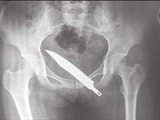

Cuchillo de 15cms en la nalga

Cuando decidió ir al médico, le hicieron una radiografía y fue encontrado en sus nalgas el arma cortopunzante de semejante longitud.

La mujer china de 26 años, fue atracada cuatro meses atrás y sin saberlo conservó la pieza de metal en su cuerpo.